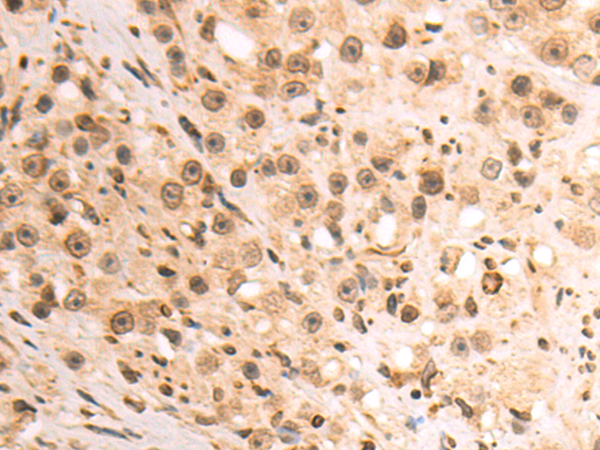

分类: 科研抗体货号: P07183别名: MCPH12; PLSTIRE应用: WB,IHC反应种属: Human, Mouse

分类: 科研抗体货号: P07191别名: GPE1BP; IG/EBP-1应用: WB,IHC反应种属: Human, Mouse, Rat

分类: 科研抗体货号: P07182别名: LIS7; PSSALRE应用: WB,IHC反应种属: Human, Mouse, Rat

分类: 科研抗体货号: P07190别名: CEACAM3, R29124_1应用: IHC反应种属: Human

分类: 科研抗体货号: P07203别名: MCL; MPCL; CD368; CLEC6; CLEC-6; CLECSF8; Dectin-3应用: WB,IHC反应种属: Human

分类: 科研抗体货号: P07181别名: CMM3; PSK-J3应用: WB,IHC反应种属: Human, Mouse, Rat

分类: 科研抗体货号: P07187别名: KIP1; MEN4; CDKN4; MEN1B; P27KIP1应用: WB,IHC反应种属: Human, Mouse